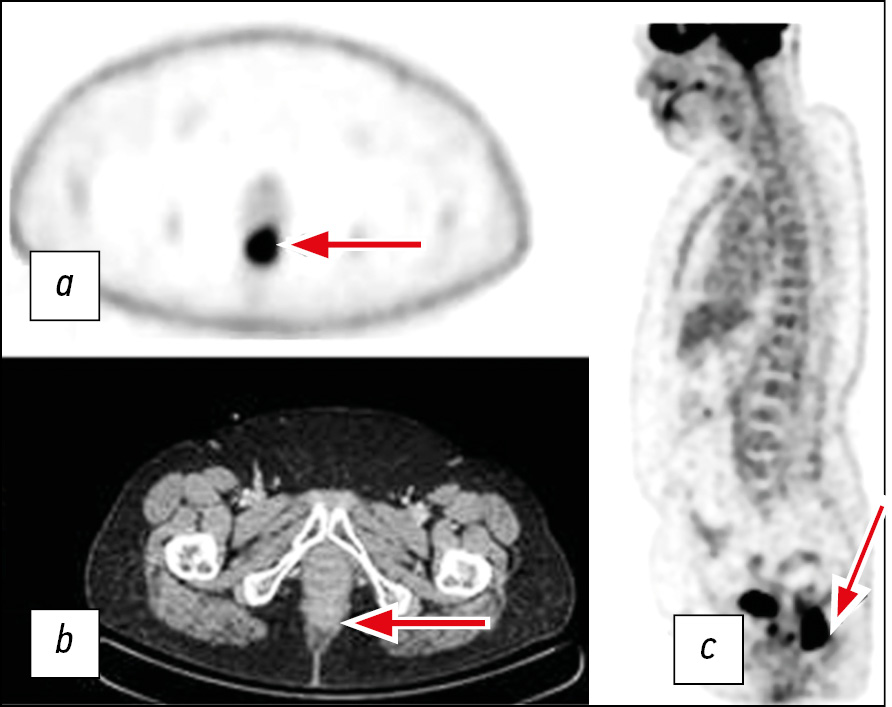

After 3 years of follow-up, the patient underwent positron emission tomography with 18F-fluorodeoxyglucose combined with computed tomography because of an increase in the level of tumor markers (Fig. 3). The results revealed a tumor with a length of 43 mm (SUVmax[2] 27.1) at the level of the lower ampullar rectum. On the basis of these results, the patient was admitted to the clinic of the A.F. Tsyba National Medical Research Radiological Center for surgical treatment in the scope of laparoscopic abdominal perineal resection.

Fig. 3. Positron emission tomography with 18F-fluorodeoxyglucose combined with computed tomography: a ― mono-mode positron emission tomography at the tumor level (arrow); b ― computed tomography at the tumor level (arrow); c ― three-dimensional reconstruction with a focus of 18F-fluorodeoxyglucose hyperfixation in the lower ampullar rectum (arrow).